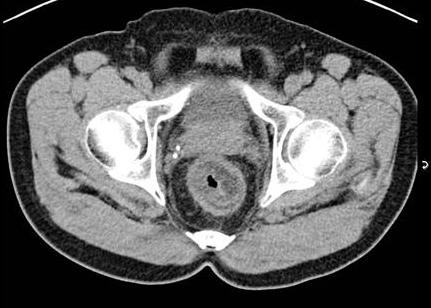

. Image TDM du maladie de

Crohn dans phase aigue est image

de epaissisement parietale avec oedeme sous muqueuse

discontinunite et signe de peigne " comb sign ". En phase

chronique cicatricielle ,aspect radiologique est image

epaissisement homogene de la paroi avec infiltration graisseuse parietale ou mesenterique

en forme de image de cible " fat halo sign". Stenose ,fistule et

abces sont des images de sa complication .

Stenose epaisissement colique

gauche et sigmoidienne avec halo graisseux d'une

maladie de Crohn . Image de hypervascularisation et

infiltration de la graisse sous-muqueuse , aspect en

peigne " Comb sign ". Image TDM en coupe coronale |

|

Image de

hypervascularisation " Comb sign " et epaissisement

de la paroi du ileon se voyait si nette sur les

coupe TDM axiale |